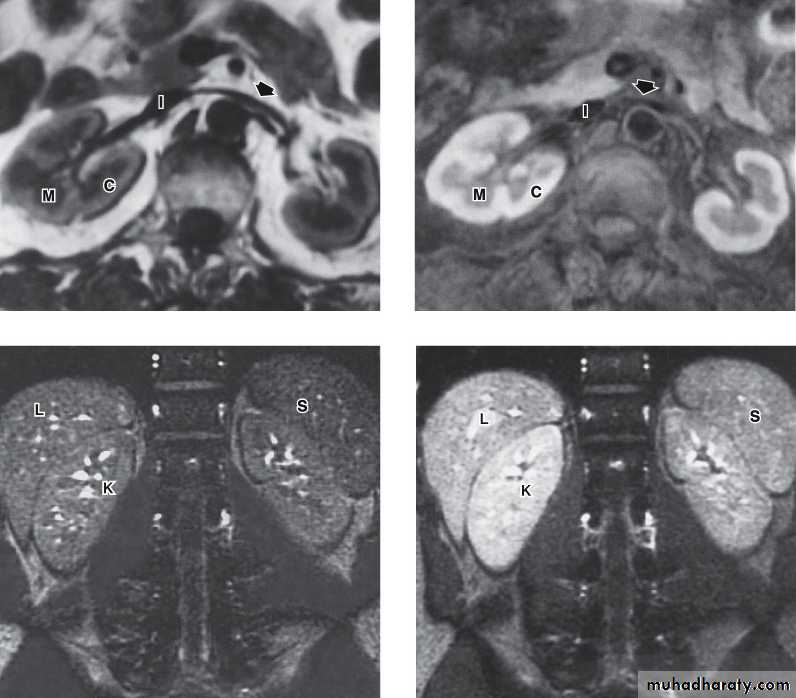

MAGNETIC RESONANCE IMAGING (MRI)Protons within the body can be thought of as small, spinning bar magnets. Hydrogen has a single proton. When a patient is placed in a large magnetic field, the hydrogen protons within the body align, and this alignment leads to the formation of a net magnetic vector within the patient.

Contrast: Gadolinium

No

radiation